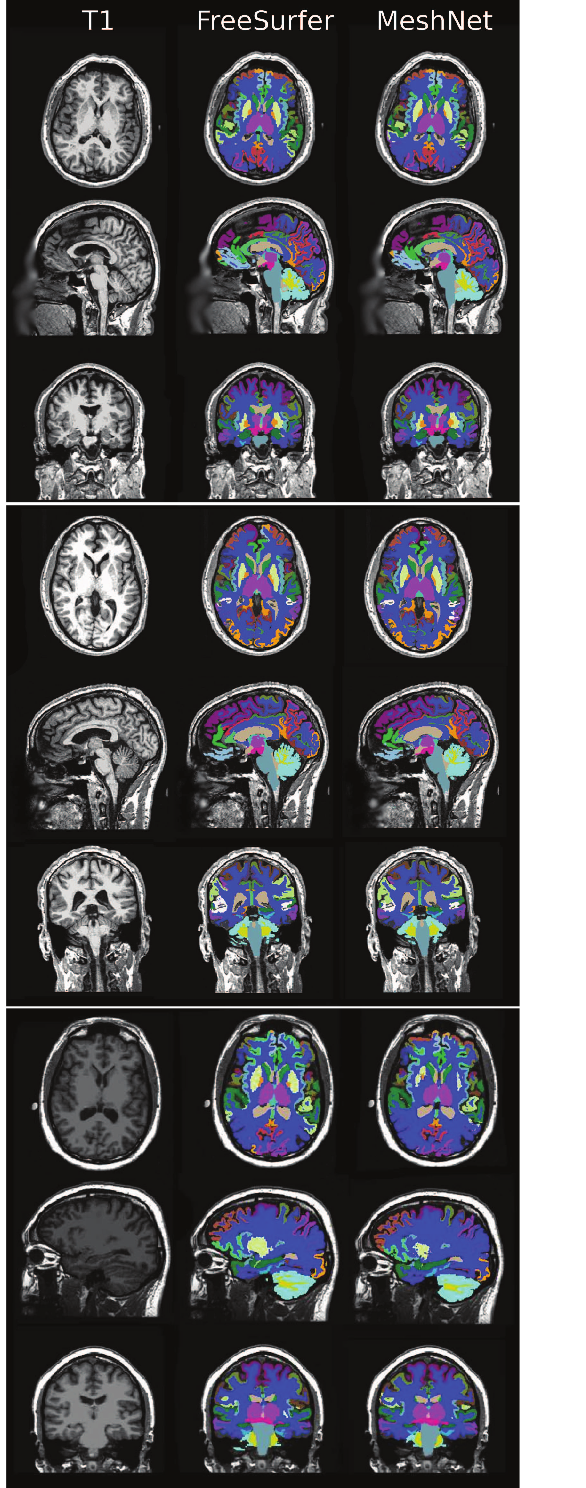

Performance on 334334334 testing subject from FBIRN dataset is shown in Figure 10 and Figure 11. For comparing its performance we also show results on HCP dataset. Segmentation examples is shown in Figures 12. To remind FBIRN dataset has not just healthy subjects, but also patients with schizophrenia. Model shows similar performance by FBIRN dataset’s sites in Figure 13 and Figure 14.

Refer to caption

Figure 12: Segmentation example for 1 healthy subject and 2 patients with schizophrenia from FBIRN dataset. Face was blurred manually after performing segmentation.